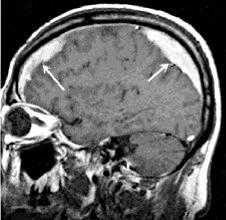

Решающими методами в диагностике субдуральной гематомы являются КТ и МРТ головного мозга. В диагностике острых гематом предпочтение отдается КТ головного мозга, которая в таких случаях выявляет однородную зону повышенной плотности, имеющую серповидную форму. С течением времени происходит разуплотнение гематомы и распад кровяных пигментов, в связи с чем через 1-6 нед. она перестает отличается по плотности от окружающих тканей. В подобной ситуации диагноз основывается на смещении латеральный отделов мозга в медиальном направлении и признаках сдавления бокового желудочка.

При проведении МРТ может наблюдаться пониженная контрастность зоны острой гематомы; хронические субдуральные гематомы, как правило, отличаются гиперинтенсивностью в Т2 режиме. В затруднительных случаях помогает МРТ с контрастированием. Интенсивное накопление контраста капсулой гематомы позволяет дифференцировать ее от арахноидальной кисты или субдуральной гигромы.